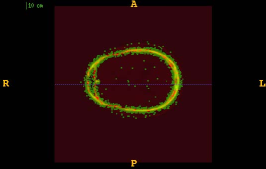

Figure 1 shows the examples of pixel selection masks generated using tested approaches at the highest resolution level for pixel sampling rate 0.5%. It is obvious that the samples generated with the URS approach are extremely spread, whereas the samples generated with the GMS approach are overly concentrated along the gradient magnitude structures present in the image. The proposed approach produces samples that balance those two extremities.